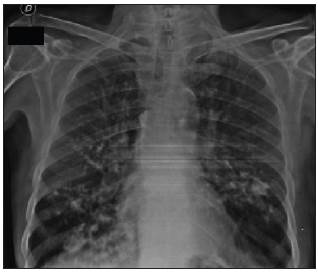

A 67-year-old male with a history of chronic obstructive pul monary disease and heavy smoking consulted due to progressive worsening of his dyspnea over the previous week along with a dry cough and unquantified fever at home. A chest x-ray showed bilateral calcified micronodules. A high-resolution computerized tomography confirmed these findings. The diagnosis was confirmed by the histological results of a bronchoalveolar lavage showing characteristic laminar microliths.

Pulmonary alveolar microlithiasis is a rare hereditary pul monary disease characterized by microcalcifications within the alveolar spaces 1. It is caused by mutations of the SCL34A2 gene which encodes the phosphate cotransporter in type II alveolar cells. This results in increased phosphate and calcium in lung surfactant, which leads to the formation and deposition of microliths within the alveoli as well as in other parts of the body 2. The definitive diagnosis requires histological identification of the microliths 3.